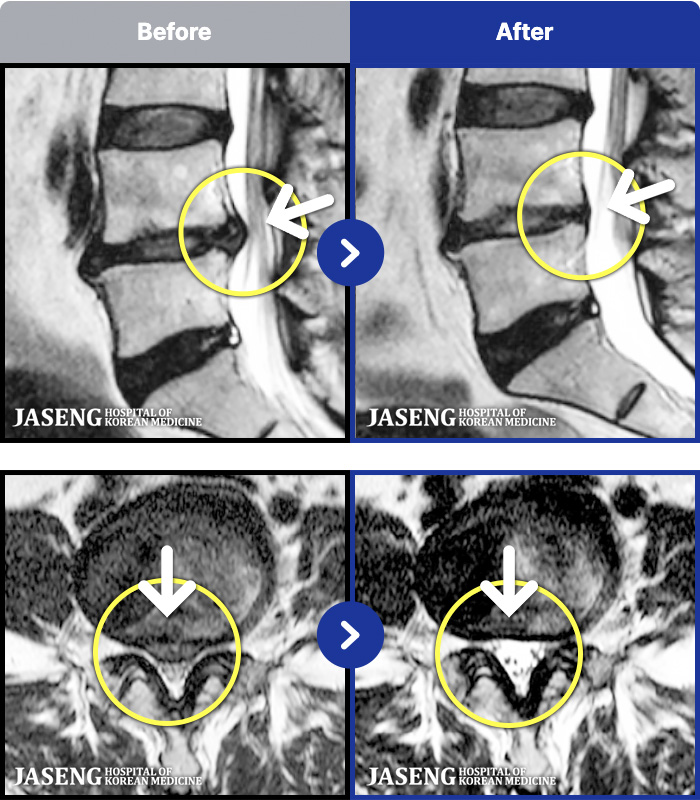

MRI ġ

1,237 MRI ũ ʸ Ȯϼ.